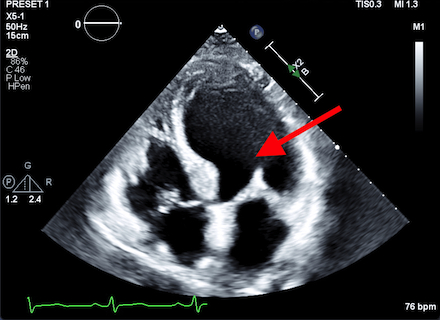

Case Discussion: A 71-year-old postmenopausal woman presented with acute dyspnea and elevated troponin (2900 pg/mL). Her history included traumatic SAH three months prior with a normal echocardiogram at that time. Electrocardiogram showed non-specific T-wave changes . Transthoracic echocardiography revealed severe left ventricular dysfunction (ejection fraction 25-30%) with apical ballooning and mid-to-apical hypokinesis, consistent with TTS . Coronary angiography confirmed non-obstructive coronary arteries. No recent stressors or acute neurological events were identified, suggesting a delayed TTS linked to the prior SAH. Heart failure therapy was initiated; follow-up echocardiography is pending.